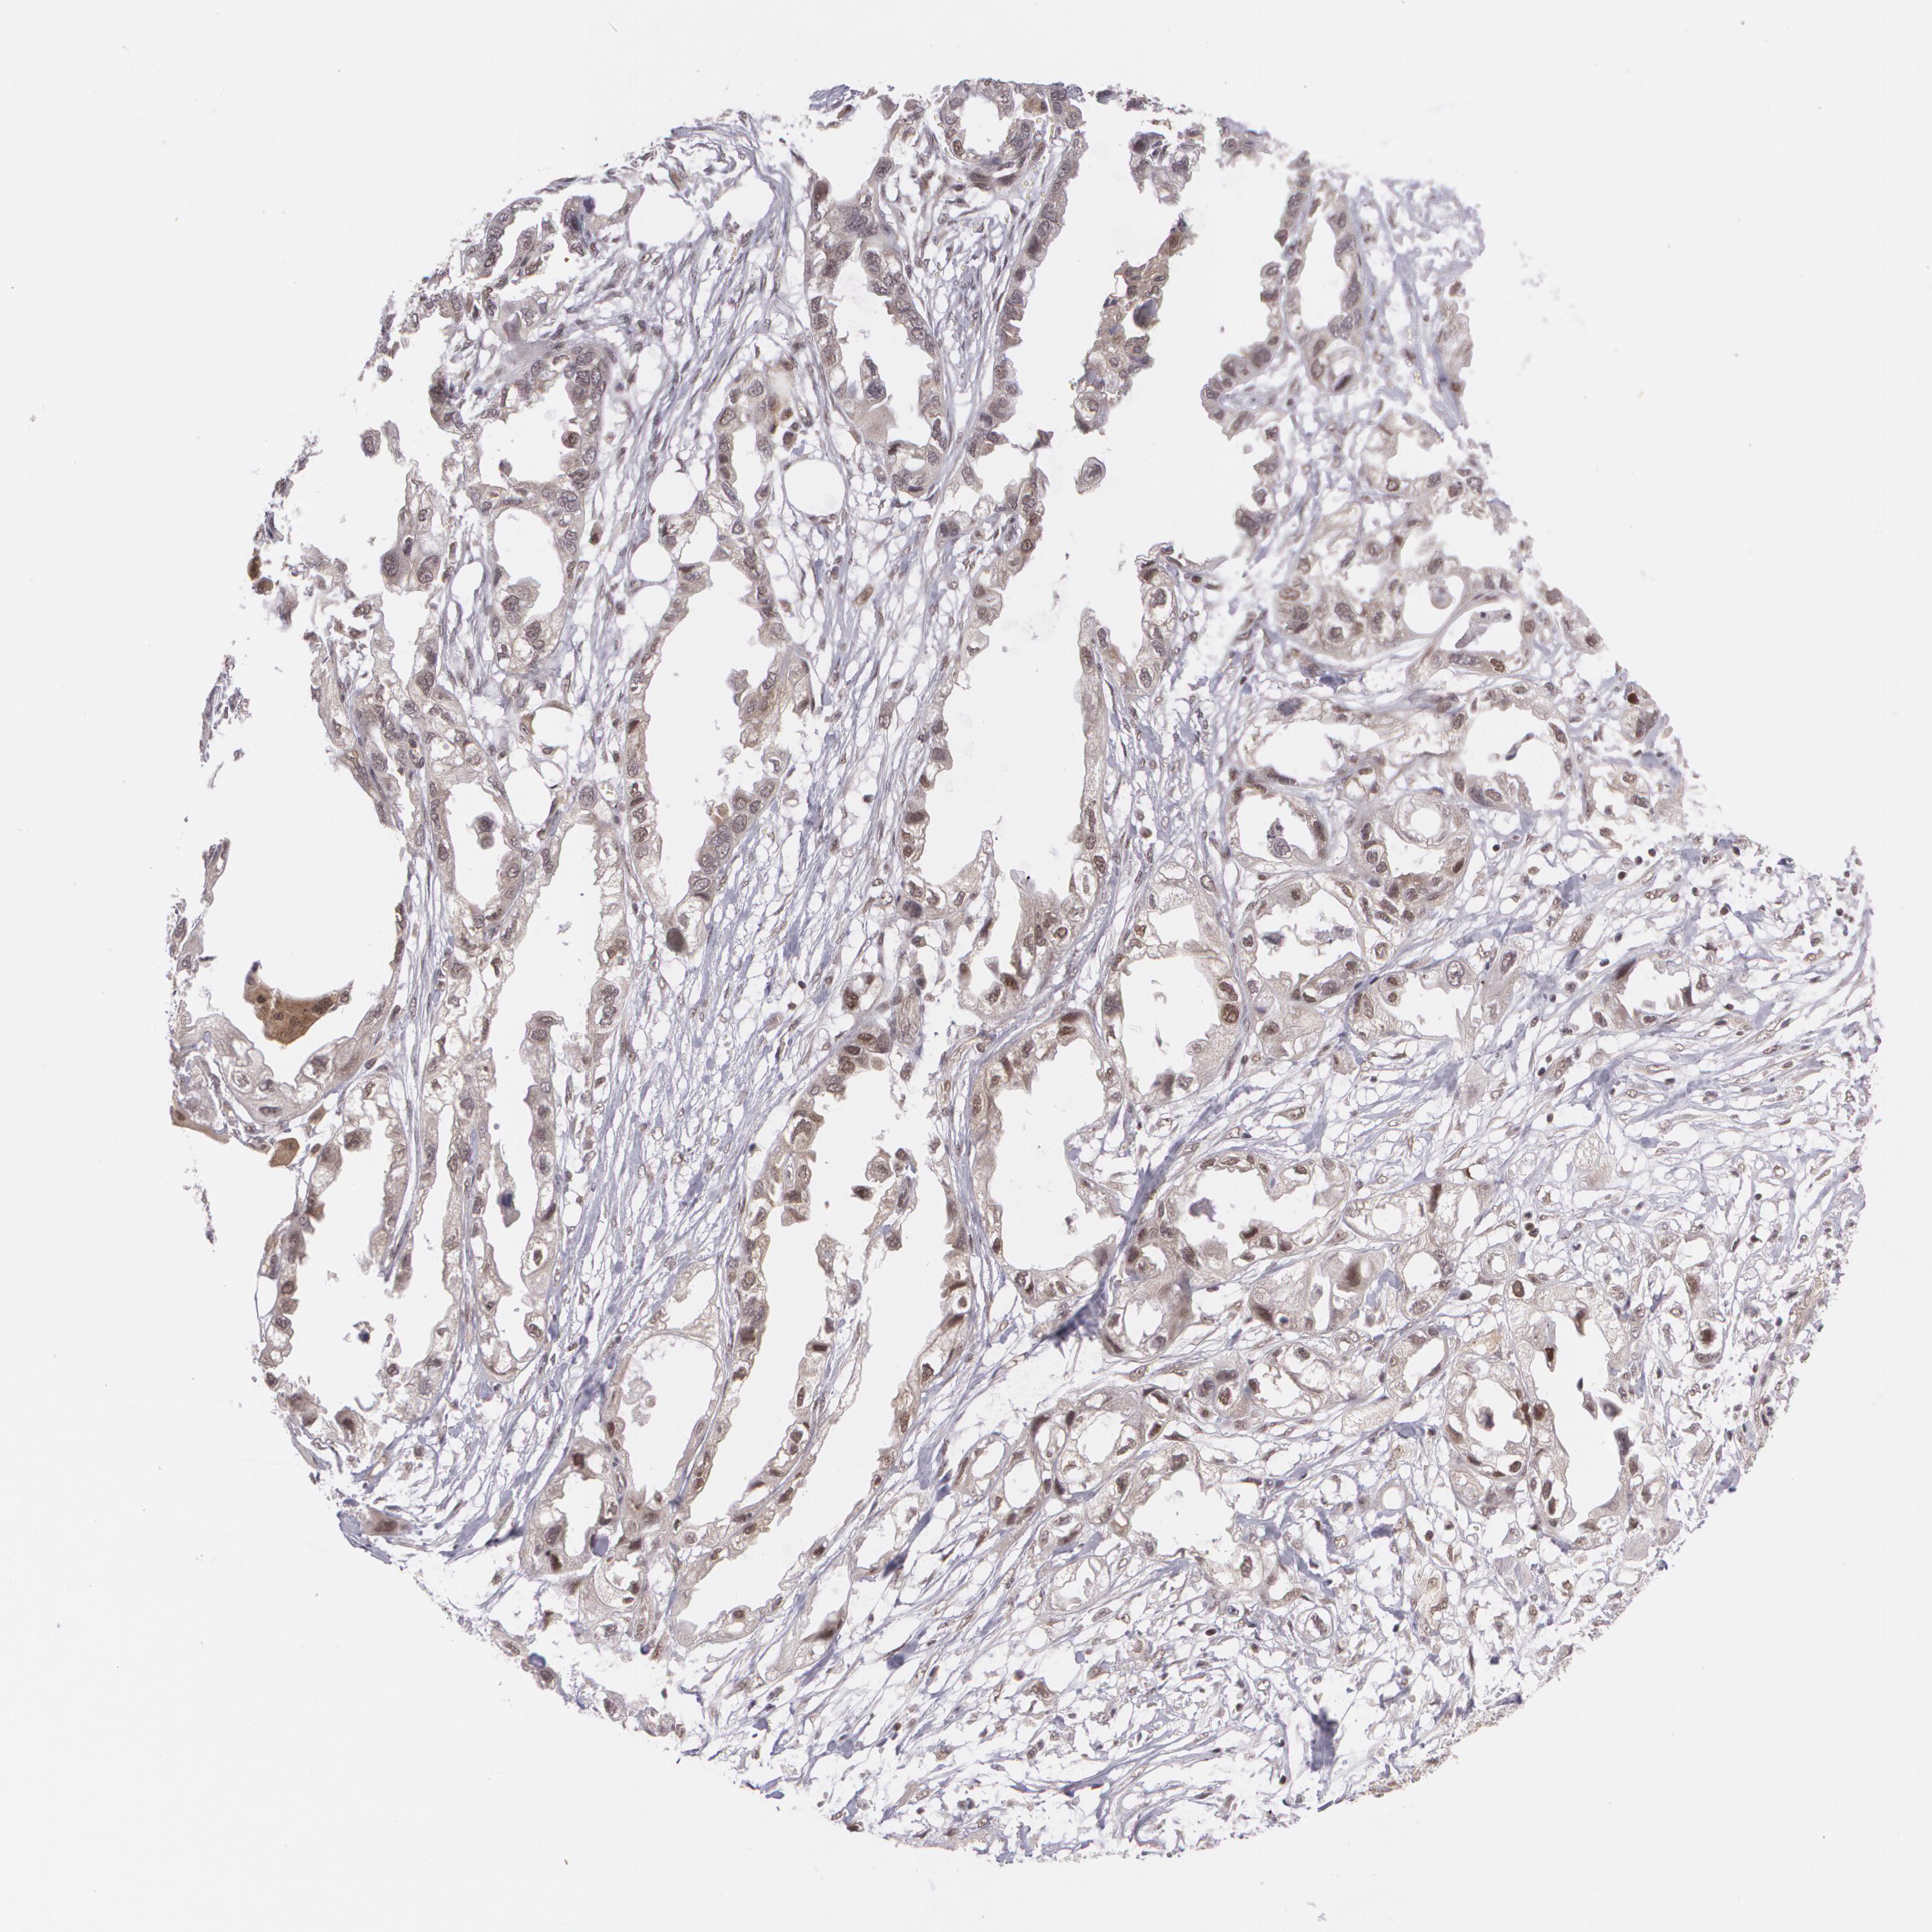

ENDOMETRIAL CANCER - Protein expressioni

A mouse-over function shows sample information and annotation data. Click on an image to view it in a full screen mode. Samples can be filtered based on level of antibody staining by selecting one or several of the following categories: high, medium, low and not detected. The assay and annotation is described here.

Note that samples used for immunohistochemistry by the Human Protein Atlas do not correspond to samples in the TCGA dataset.

Antibody stainingi

Antibody staining in the annotated cell types in the current human tissue is reported as not detected, low, medium, or high, based on conventional immunohistochemistry profiling in selected tissues. This score is based on the combination of the staining intensity and fraction of stained cells.

Each image is clickable and will lead to virtual microscopy that enables deeper exploration of all samples and also displays staining intensity scores, fraction scores and subcellular localization as well as patient and tissue information for each sample.

Antibody HPA024578

Antibody CAB002677

Staining

High

Medium

Low

Not detected

Intensity

Strong

Moderate

Weak

Negative

Quantity

>75%

75%-25%

<25%

None

Location

Nuclear

Cytoplasmic/membranous

Cytoplasmic/membranous,nuclear

Adenocarcinoma, NOS

Adenocarcinoma, metastatic, NOS

Neoplasm, malignant, NOS